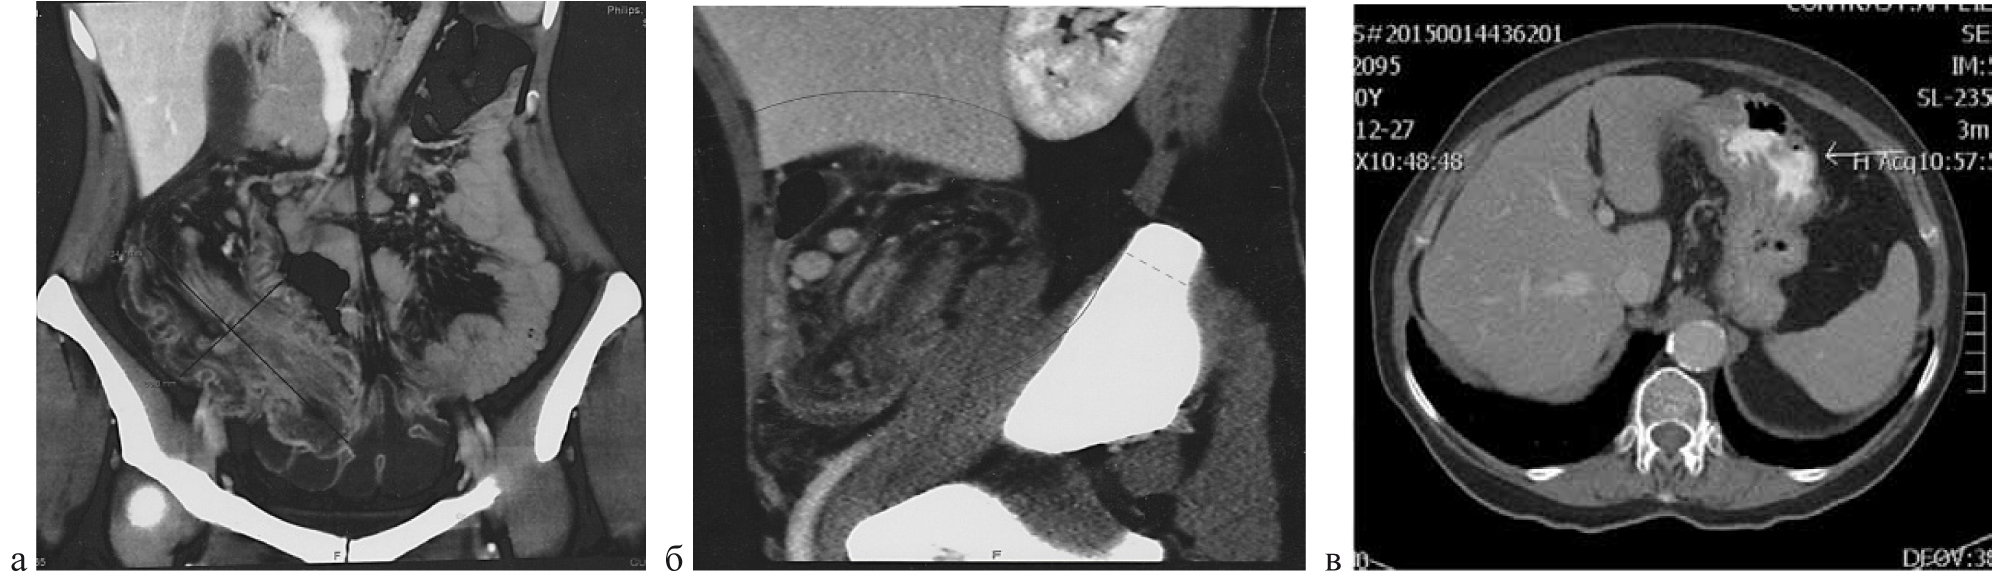

Наиболее информативным методом обследования при ООТК мы считаем МСКТ брюшной полости в режиме ангиографии, которая у 31 пациента (59,6 %) позволила не только диагностировать, но и стадировать ООТК, выявить характерные признаки, соответствующие гистологической структуре опухоли. Выявлены общие патогномоничные признаки ООТК: при эндофитном росте опухоли локальные изменения проявлялись утолщением стенки кишки более 10–15 мм и сужением ее просвета, экзофитный тип проявляется узлом, растущим в просвет кишки. При контрастном усилении ткань опухоли накапливала контрастный препарат более интенсивно, чем подслизистый и мышечный слои неизмененной стенки кишки. Лимфомы на компьютерных томограммах проявлялись либо узловой инфильтрацией, либо утолщением стенки кишки в пределах сегмента, при этом накопление препарата происходило преимущественно по периферии опухоли в виде тонкого ободка, что отражало окрашивание неизменной слизистой оболочки. Саркомы представляли неоднородные по структуре образования с признаками инфильтративного роста. Неоднородность была обусловлена, как правило, массивным некрозом и последующим развитием кистозной дегенерации. Для сарком, при контрастном усилении, было характерно интенсивное, неоднородное окрашивание опухоли и значительная инфильтрация окружающей кишку жировой клетчатки. Гастроинтестинальные стромальные опухоли (GIST) на МСКТ имели вид ограниченного мягкотканого экзофитного образования, с признаками экспансивного роста. Доброкачественные GIST имели однородную структуру, при контрастном усилении интенсивно окрашивались, что часто служило их «визитной карточкой». Злокачественные GIST при контрастном усилении чаще проявлялись неоднородной структурой, что объясняется развитием в структуре опухоли некротических изменений и кистозной дегенерации (рис. 5).

Все пациенты были оперированы, 73 срочно и экстренно, 28 в отсроченном порядке. Резектабельность при этом составила 86,8 %. Гистологическая структура опухолей, характер осложнений и локализация представлена в табл.

Рис. 5. МСКТ брюшной полости в режиме ангиографии: а) эндофитная опухоль в инвагинате; б) лимфома подвздошной кишки; в) аденокарцинома двенадцатиперстной кишки